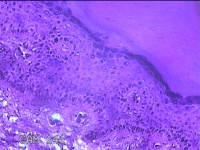

左足部包块

性别

女

年龄

34岁

临床诊断

皮下囊肿

一般病史

发现左足部包块4年余,无明显疼痛及不适。

标本名称

大体所见

灰白暗红色组织1.8x1.1x0.8cm一块,表面带梭形皮肤1.8x0.8cm,皮下见包块1。8x0.8x0.7cm一个,切开包块呈实性,切面灰白粉红色,质软。

图2